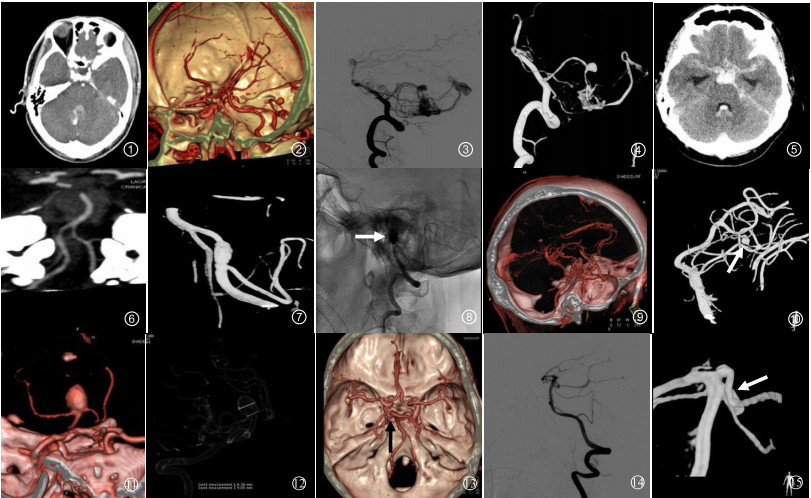

6例3D-CTA假阳性结果中,3例(50.0%)椎动脉V4段完全血栓机化CTA误诊为动脉瘤,1例(16.7%)小脑下动脉复合体误诊为小脑后下动脉瘤,2例(33.3%)小脑动静脉畸形合并小脑前下动脉动脉瘤漏诊为单纯囊状动脉瘤。5例(83.3%)动脉瘤直径≤5 mm,1例(16.7%)动脉瘤直径 > 5 mm,见图 1~4。

图 1 图 1~4 病例1:男,40岁,突发头痛伴呕吐1 d余。CTA原始轴位图像(图 1)示第四脑室后方囊袋状对比剂充盈影,周围见高密度出血,结合3D-CTA VR图像(图 2)考虑右侧小脑前下动脉出血性动脉瘤。2D-DSA及3D-DSA均可见动脉期有静脉早显现象,小脑前下动脉囊状动脉瘤的后方伴有畸形血管团和增粗的引流静脉,提示小脑动静脉畸形合并小脑前下动脉动脉瘤形成(图 3~4) 图 5~8 病例2:男,48岁,突发剧烈头痛、呕吐1 d。查头颅CT提示SAH、脑室积血(图 5)。MIP图像见左侧椎动脉颅内段局部血管痉挛改变,未见明确动脉瘤(图 6)。DSA显示左侧椎动脉V4段(小脑后下动脉分叉处以远)串珠征及双腔征改变,提示夹层动脉瘤(图 7 3D-DSA;图 8急诊栓塞后DSA,白箭头示弹簧圈) 图 9~10 病例3:女,43岁,突发头疼2 d。自发性SAH患者,3D-CTA检查均未见动脉瘤(图 9)。3D-DSA清晰可见左侧小脑上动脉远段分支小囊状染色,诊断为左侧小脑上动脉远段小动脉瘤破裂(图 10, 白箭头示) 图 11~12 病例4:男,58岁,突发头痛伴恶心、呕吐1 d。3D-CTA和3D-DSA均可清楚地显示基底动脉尖直径9 mm动脉瘤,并具有更直观的3D效果,真实显示了瘤体形态、瘤颈及动脉瘤与载瘤动脉的空间关系(图 11 CTA VR图像;图 12 DSA三维透明法) 图 13~15 病例5:女,54岁,突发意识障碍伴头痛、呕吐2 d。3D-CTA考虑左侧大脑后动脉起始部动脉瘤(图 13, 黑箭头示)。12 h后行常规DSA及3D-DSA检查(图 14~15)。因注入的对比剂量增加,对细节的显示更清楚,DSA准确显示动脉瘤位于左侧小脑上动脉近段(图 15, 白箭头示) |

42例3D-CTA假阴性结果中,12例(28.6%)椎动脉V4段,18例(42.9%)小脑后下动脉,6例(14.3%)小脑前下动脉,3例(7.1%)小脑上动脉以及2例(4.8%)基底动脉动脉瘤未诊断,1例(2.4%)小脑上动脉动脉瘤表现为同侧大脑后动脉动脉瘤。37例(88.1%)动脉瘤直径≤5 mm,其中24例(57.1%)动脉瘤直径≤3 mm,13例(31.0%)动脉瘤直径 > 3 mm且≤5 mm,另外5例(11.9%)动脉瘤直径 > 5 mm,图 5~10。

本研究发现3D-CTA显示颅内后循环各部位的出血性动脉瘤均有很高的特异度,对基底动脉动脉瘤、大脑后动脉动脉瘤诊断的敏感度和准确率较高(图 11~12病例4),但是,显示椎动脉V4段动脉瘤、小脑后下动脉动脉瘤、小脑前下动脉动脉瘤及小脑上动脉动脉瘤的敏感度均低于85%。笔者认为这可能是由于椎动脉V4段动脉瘤、小脑后下动脉动脉瘤、小脑前下动脉动脉瘤及小脑上动脉动脉瘤靠近颅底,CTA图像易受颅底骨质伪影干扰;部分载瘤动脉血管较细,血流相对较少,特别是二级以下分支血管,注入的对比剂经血流稀释后显影不清;也可能是由于动脉瘤破裂出血后,周围的氧合血红蛋白对血管壁的刺激,加之红细胞在其降解过程中一些分解产物和神经递质释放的影响,引起载瘤动脉血管痉挛改变,使CTA检出困难。

与3D-DSA结果进行对照研究,发现存在一些假阳性和假阴性的结果值得进一步讨论。本研究中,3例CTA显示假阳性直径均 < 5 mm的椎动脉V4段动脉瘤最后被证实为完全血栓闭塞性动脉瘤,1例小脑下动脉复合体由于走行迂曲、成襻,CTA显示为小脑后下动脉动脉瘤样表现,2例小脑动静脉畸形合并小脑前下动脉动脉瘤漏诊为单纯小脑前下动脉囊状动脉瘤。因此,对于颅内后循环动脉尤其是椎动脉内CT平扫呈高密度且CTA显示瘤样膨隆的病变,应考虑到动脉瘤完全血栓机化的可能。而对于后循环血管变异或合并有其他血管畸形时,应注意在CTA后处理过程中多方位、多角度观察,仔细辨别是否存在假象,避免造成误诊的可能。

由于存在重叠的骨性结构和复杂的血管解剖,使动脉瘤因颅底骨质伪影、血管扭曲或大血管遮挡,导致CTA对于靠近颅底的小动脉瘤显示较困难。在假阴性结果中,绝大多数动脉瘤直径小于5 mm,约占88.1%。这些漏诊的动脉瘤主要位于椎动脉、小脑后下动脉、小脑前下动脉及小脑上动脉,特别是位于上述动脉远段分支处的动脉瘤,3D-CTA难以显示清晰。另外,颅内动脉瘤及其血管壁的搏动可使血管表面重建时血管壁显示不完全,动脉瘤早期破裂出血会引起载瘤动脉及其近端血管痉挛改变,对于直径 < 5 mm动脉瘤和夹层动脉瘤有漏诊的可能。本研究中夹层动脉瘤70例,均位于椎动脉V4段,其中12例(占17.14%)3D-CTA诊断时被忽略,未见文献报道的串珠征、线样征或双腔征改变。因此,对于颅内后循环动脉邻近颅底的、直径 < 5 mm的远段分支处动脉瘤及夹层动脉瘤,急诊CTA检查容易漏诊。

本研究中1例小脑上动脉近段动脉瘤误诊为同侧大脑后动脉动脉瘤(图 13~15病例5),与3D-DSA对照分析,发现此例患者3D-CTA图像上左侧大脑后动脉未显影。笔者认为这可能与CTA检查时靶血管的对比剂浓度较低或血流动力学影响有关。由于DSA超选至双侧椎动脉对颅内后循环动脉进行检查,而CTA是从外周静脉注入对比剂经肺循环后对靶血管薄层扫描。因此,与DSA相比,CTA流入靶血管的对比剂浓度低,对血流动力学影响轻微,故对侧支循环情况显示不如DSA。